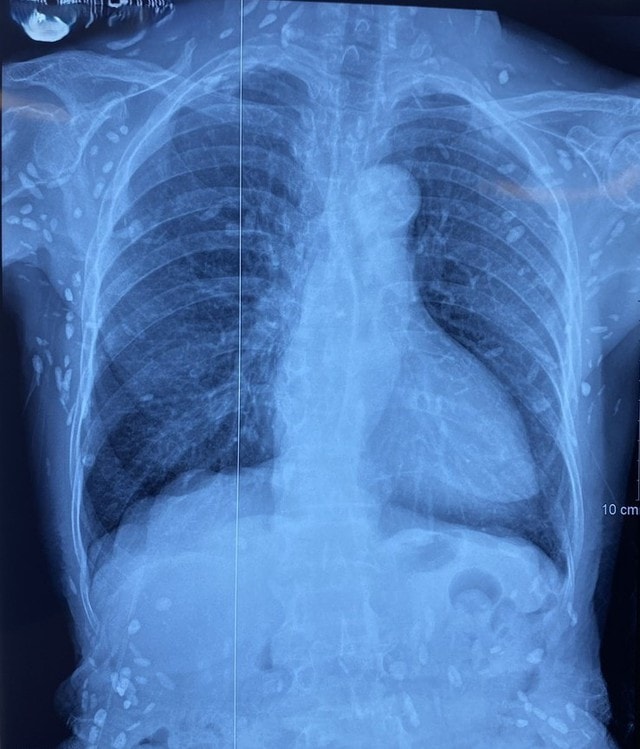

Người phụ nữ 77 tuổi được chuyển lên từ tuyến trước vì rối loạn ý thức đe dọa suy hô hấp, hình ảnh cắt lớp vi tính sọ não và X-quang ngực cho thấy rất nhiều nốt cản quang trong nhu mô não và dưới da vùng ngực-bụng.

Người bệnh được chuyển lên từ tuyến trước vì rối loạn ý thức đe dọa suy hô hấp, hình ảnh cắt lớp vi tính sọ não và X-quang ngực cho thấy rất nhiều nốt cản quang trong nhu mô não và dưới da vùng ngực-bụng.

Một vài u cục với kích thước tương ứng có thể sờ thấy dưới da vùng ngực và cánh tay của người bệnh.

Mặc dù xét nghiệm kháng thể IgM với sán dây lợn âm tính, các tổn thương trên X-quang gợi ý người bệnh trước đây bị nhiễm ấu trùng sán dây lợn, sau đó các nang sán trở nên vôi hóa và tồn tại lâu dài trong tổ chức. Người bệnh được điều trị theo phác đồ bệnh chính, đáp ứng và ra viện tiếp tục điều trị theo tuyến.

Nang sán dây lợn có thể tự thoái hóa hoặc bị vôi hóa, tạo nên nhiều hình ảnh cản quang phát hiện được trên phim X-quang như trường hợp bệnh nhân trên.